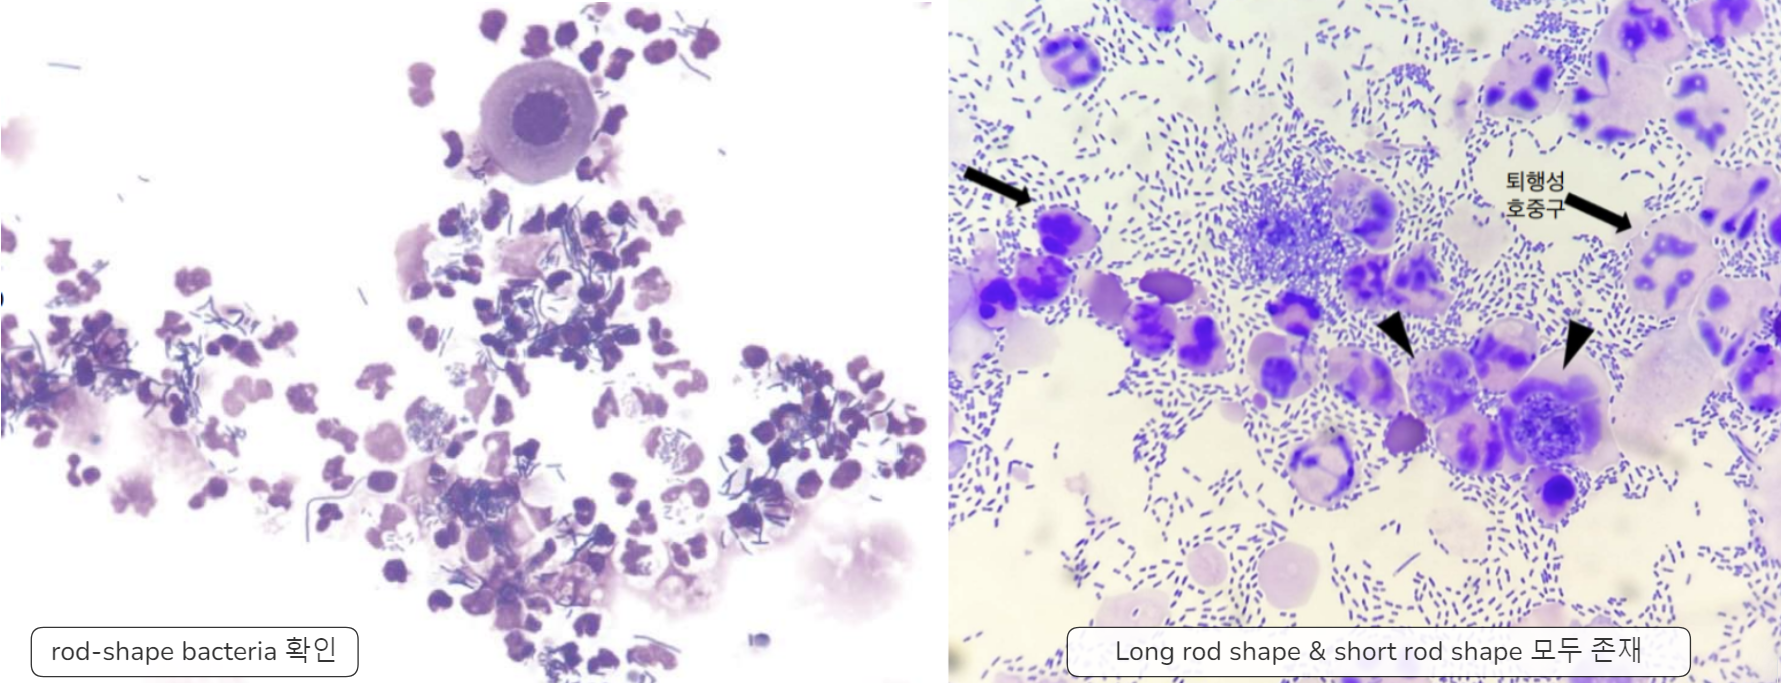

| 침전물 검사 (요침사 검사) | - 염증 세포 : >5 WBC/400배 시야 - 세균 확인 : 수, 모양, intra/extracellular, phagocytosis 확인 등 - Wet 검사 → 결석, dry에서 확인되지 않은 이상 세포, RBC 산재 정도  |

- Cytology → 간균, 단간균이 다수 관찰된다

| Cytology | |||

|---|---|---|---|

| Gram (-) 간균(rod), 단간균(bacillus) |  | Cephalosporins 우선적으로 고려 | ==E. coli, Enterobacter, Klebsiella, Proteus==, etc. |

| Gram (+) 구균(cocci) |  | Amoxicillin, Cephalospotin 우선적으로 고려 | Staphylococcus, Streptococcus, Enterococcus, etc. |